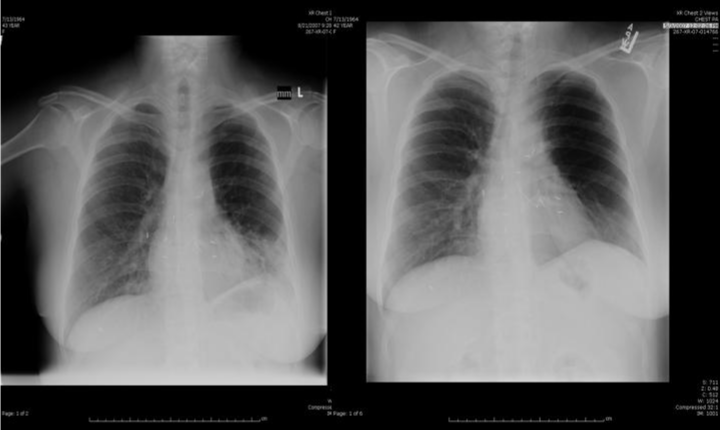

| Figure 1: 43 year old female with bilateral sequential lung transplant for IPF presents with persistent fever, chills and productive sputum despite oral antibiotics. Chest radiograph (left) indicates a new left lower lobe opacity/air space disease. Chest radiograph 6 weeks earlier (right) is viewed for comparison. Transbronchial biopsy revealed the presence of ISHLT grade A1 acute cellular rejection. |